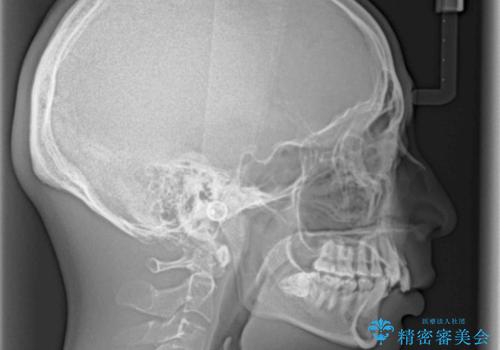

顕著な上顎の八重歯とディープバイトであったため、上顎の左右第一小臼歯を抜歯することとしました。

犬歯歯根の位置や奥歯の咬み合わせから、ワイヤー装置での治療を強くおすすめいたしましたが、ご本人の強い希望により、妥協的な仕上がりとなることを了解いただき、インビザラインにて矯正治療を行うこととしました。

ディープバイトや奥歯の咬み合わせなど、インビザライン矯正では限界がありワイヤー装置での治療に及ばない仕上がりとなりました。